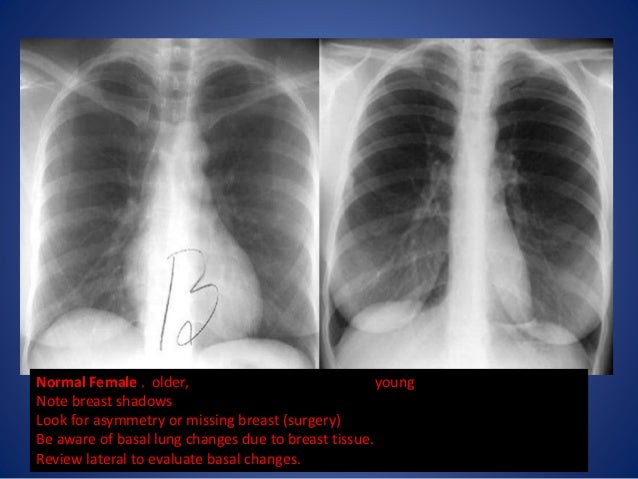

The significance of the problem in adults is not minimal. Surrounding granulation tissue and secretions can obscure the margins making it difficult to correctly identify the nature of the obstructing lesion.įoreign body aspiration is detailed extensively in children but less frequently in adults. Clinically, aspirated foreign bodies may commonly be confused with endobronchial malignancies based on the similar radiographic findings and initial gross appearances. Foreign body identified as popcorn kernel.Ĭ. Using cryotherapy, the foreign body was successfully removed and eventually identified as a popcorn kernel ( Figure 5).įigure 5. Repeat bronchoscopy was performed with results as shown in Video 1.īronchoscopy revealed a foreign body in the left upper lobe bronchus. The patient was transferred on mechanical ventilation to a tertiary care center for further evaluation of suspected endobronchial malignancy. She was electively intubated for the procedure and bronchoscopy revealed an endobronchial lesion in the LUL. The patient was admitted to the outside hospital and underwent bronchoscopy for evaluation of left upper lobe (LUL) and lingular collapse. Computed tomography image of the chest demonstrating left upper lobe (LUL) consolidation with endobronchial lesion in LUL bronchus. Computed tomography image of the chest demonstrating consolidation of the left upper lobe.įigure 4. Two cuts are provided below ( Figures 3 and 4).įigure 3. Subsequently the patient underwent computed tomography (CT) of the chest with pulmonary angiography. Lateral view on chest x-ray demonstrating left upper lobe consolidation. Posterior-anterior chest x-ray demonstrating left sided consolidation without volume loss.įigure 2. Posterior-anterior (PA) and lateral films were provided ( Figures 1 and 2).įigure 1. She presented to an outside hospital emergency department and was found to have an abnormal chest x-ray.